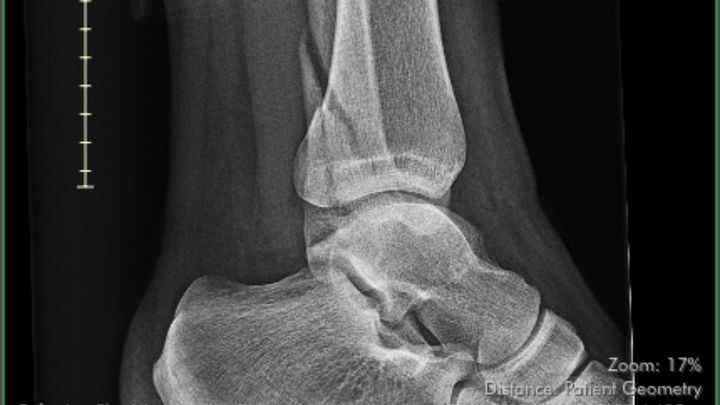

On 12/14/24 my Daughter fell and broke her ankle at 22 weeks pregnant. She was recommended surgery but with being pregnant & the difference in recovery times she opted out and has been home healing in a hard cast. She lives alone with her 3 dogs, and also her growing baby (27 weeks now) & pays all her bills off of a server/bartender income. Since the injury she has been off work. After applying for help she has been denied Short Term Disability, Unemployment, and also lost her insurance at the 1st of the new year. She is really stressed with all of her nonstop bills: rent, utilities, phone, food & dog food, etc with having no income or way to get income currently.